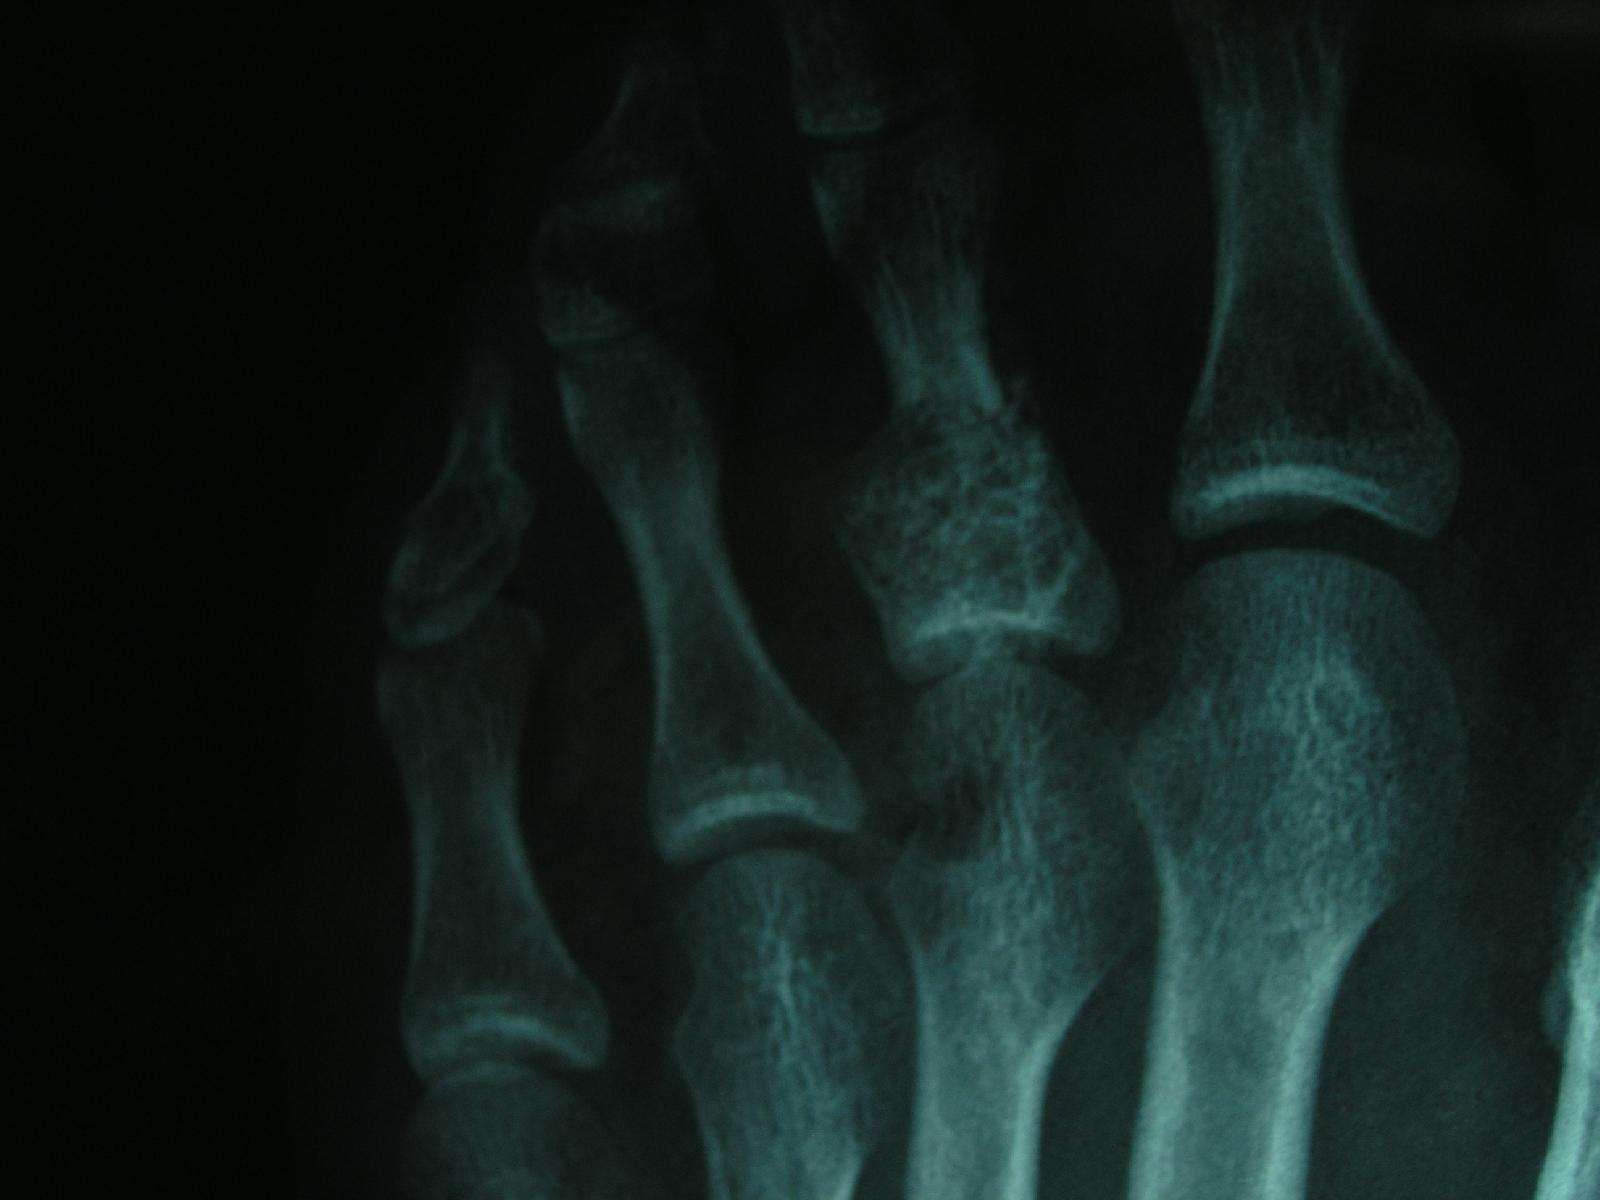

转同行:手指关节肿胀疼痛内生性软骨瘤(enchondroma)良性软骨肿瘤

内生软骨瘤(enchondroma) - 好大夫在线

内生软骨瘤(enchondroma) 4.

outcome of conservative and surgical treatment of enchondromas